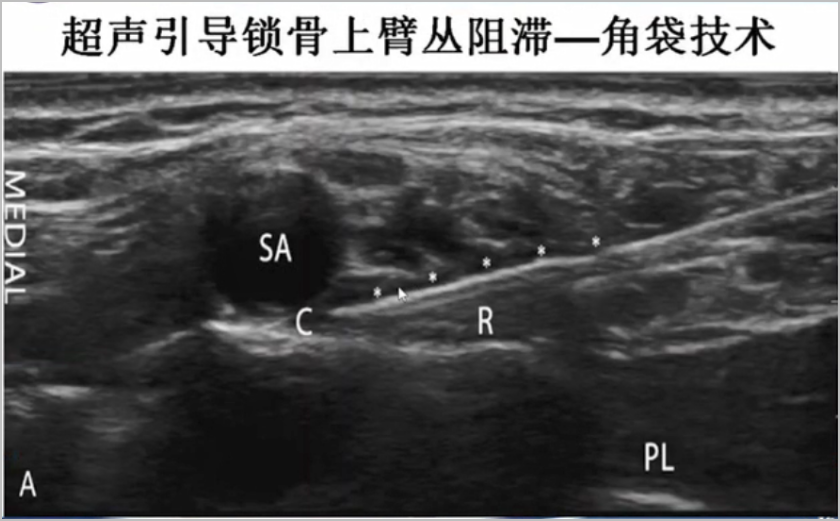

穿刺方法:平面内法,从外侧进针,2点法注射。即先穿刺到整个臂丛的深面注射一半的局麻药物,然后再穿刺到浅面注射另一半局麻药物,实现囊袋状包裹臂丛。不建议将局麻药物打在臂丛神经束之间。不推荐使用从内侧进针,因该法容易损伤锁骨下动脉。

2、为减少膈神经的阻滞,可采用角袋内注射技术,即将局麻药注入第一肋和锁骨下动脉交叉处,降低膈神经麻痹发生率。